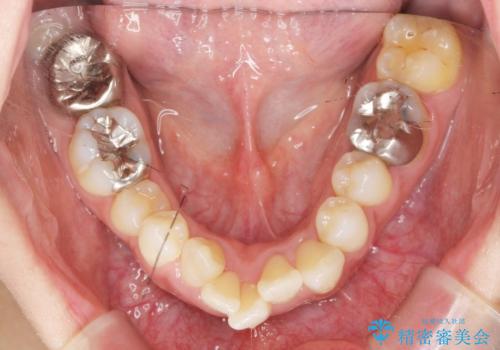

職業柄ワイヤー矯正ができない、マウスピース矯正で行う八重歯抜歯症例

- 「長年気になっている八重歯を矯正治療で治したい、ただし職業柄ワイヤー矯正は絶対にできないのでマウスピース矯正を希望。」

、と矯正治療を希望され来院されました。

通常は八重歯の抜去は行わず、小臼歯の抜去を行いワイヤー矯正を行いますが、八重歯を抜去することでマウスピースで現実的に達成できる機能的な歯並びを獲得できるよう治療計画を立案します。